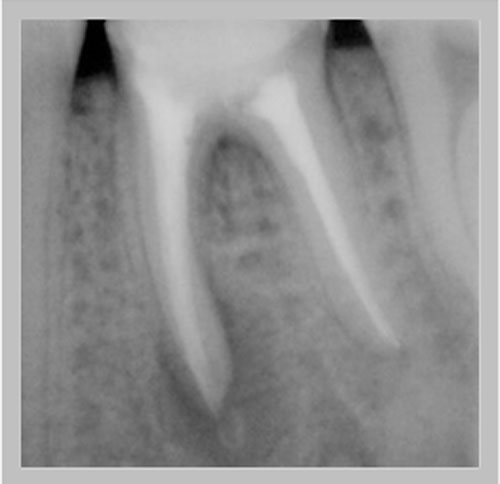

Χρόνια φλεγμονώδης περιακρορριζική βλάβη, κυρίως,

λόγω ενδοδοντικής αιτιολογίας. Μετά την ενδοδοντική θεραπεία

ακολούθησε περιοδοντική θεραπεία.

Δύο χρόνια μετά, παρατηρείται πλήρης εξαφάνιση της βλάβης.